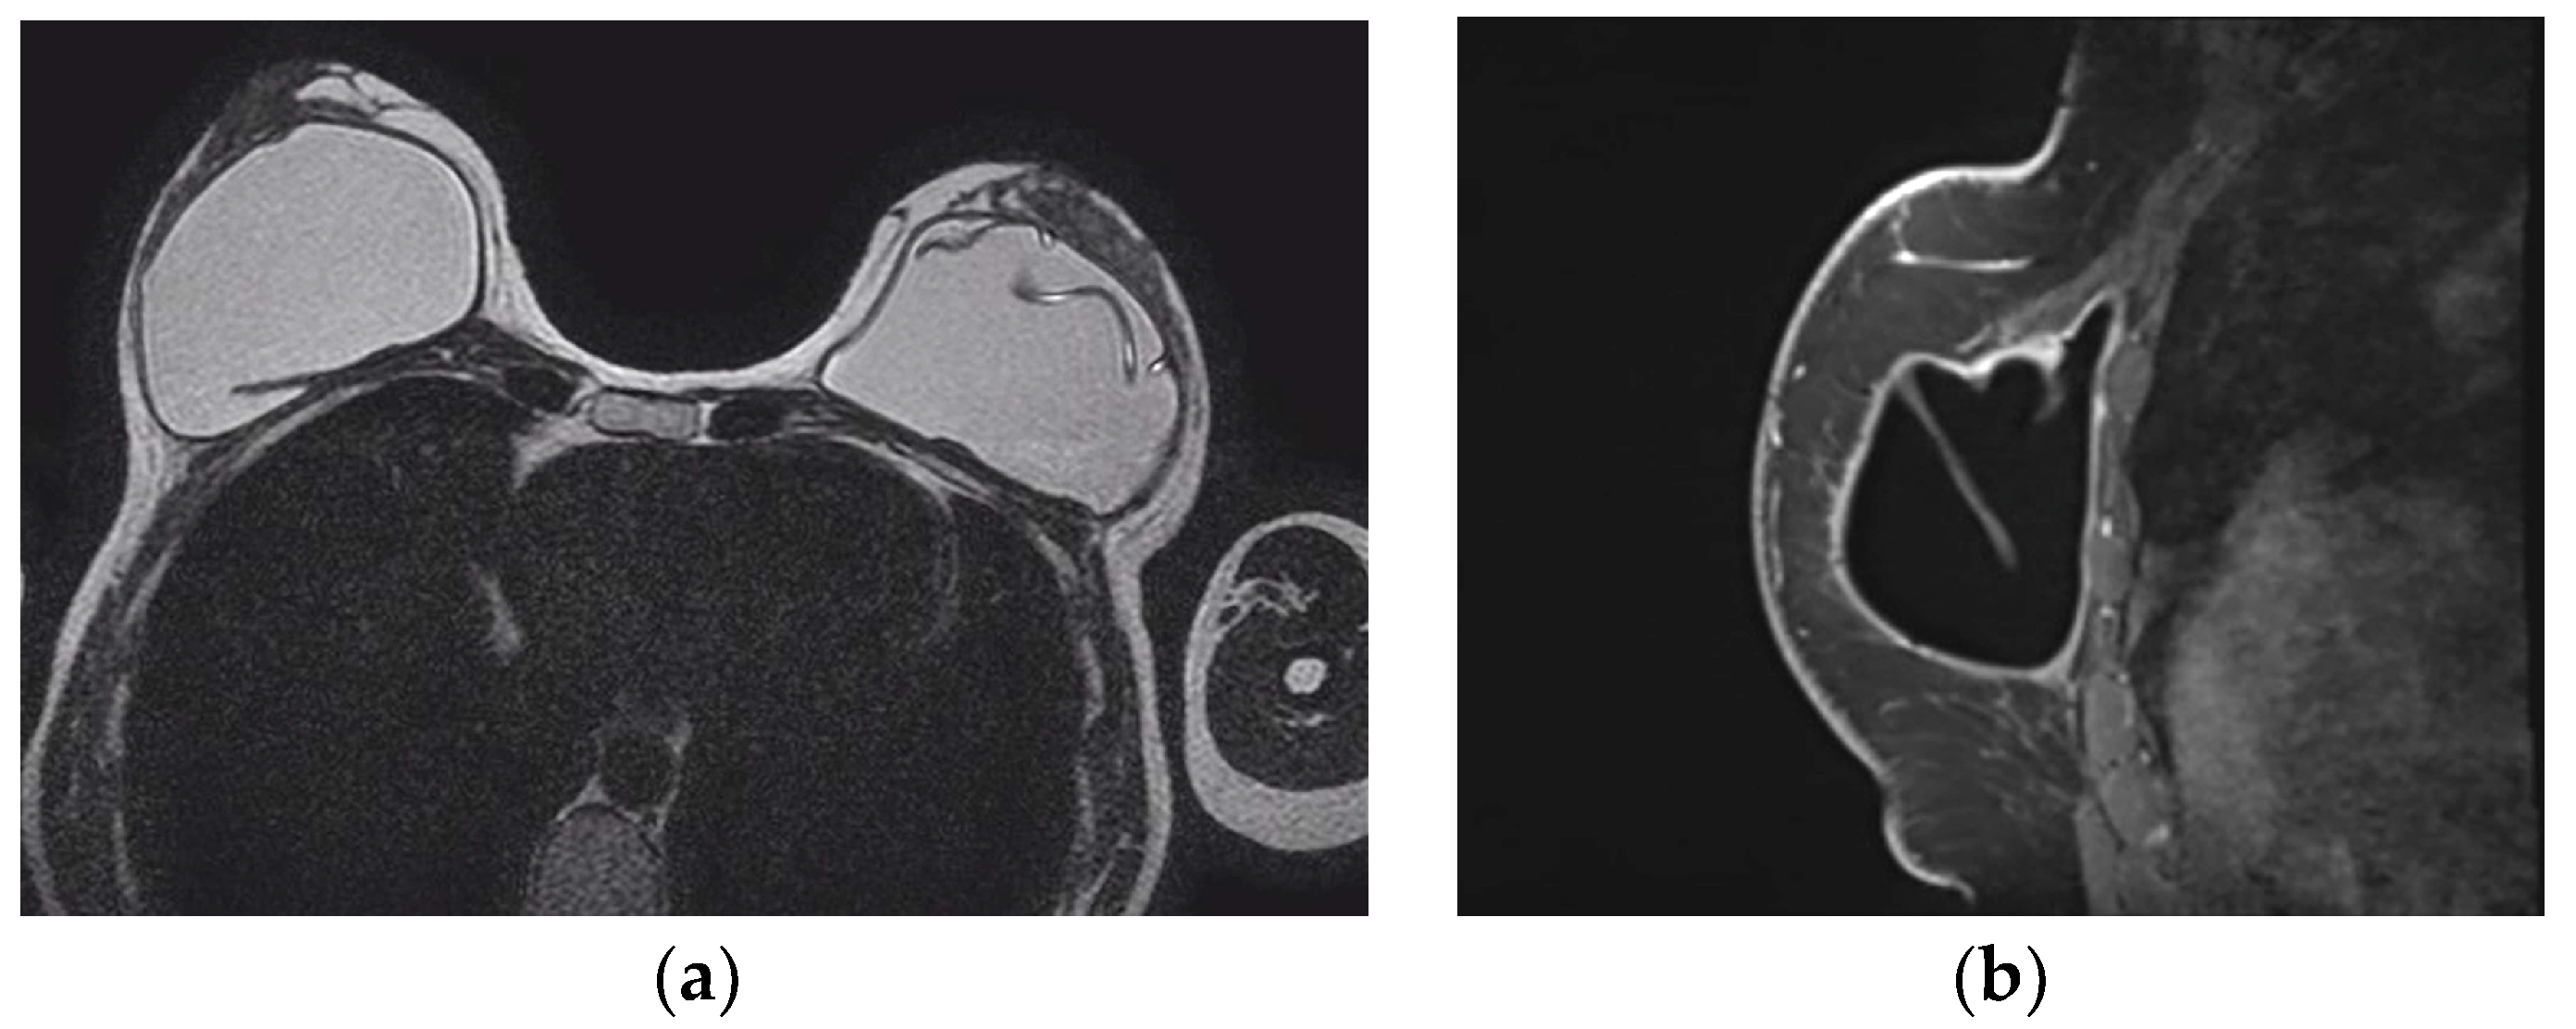

- Safvi, A. Linguine sign. Radiology 2000, 216, 838–839. [Google Scholar] [CrossRef]

- Soo, M.S.; Kornguth, P.J.; Walsh, R.; Elenberger, C.; Georgiade, G.S.; DeLong, D.; Spritzer, C.E. Intracapsular implant rupture: MR findings of incomplete shell collapse. J. Magn. Reson. Imaging 1997, 7, 724–730. [Google Scholar] [CrossRef] [PubMed]

| Definitive rupture | Linguini sign | Low signal lines within the silicone |

| Subcapsular lines | Low signal lines parallel to the capsule surrounded by silicone | |

| Possible rupture | Keyhole or teardrop Sign | Focal silicone invagination between implant shell and fibrous capsule |